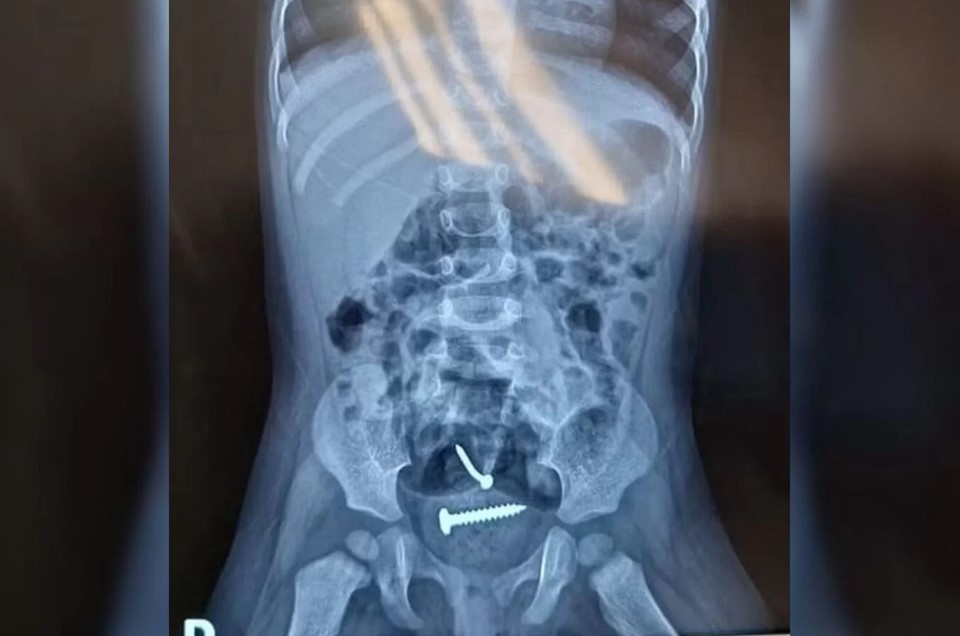

Parafusos são encontrados dentro de criança e.s.t.u.p.r.a.d.a pelo pai

Exames reveleram que, além de lesões nas partes íntimas, a menina tinha parafusos dentro do corpo. O homem foi preso nesta 3ª (19/12)